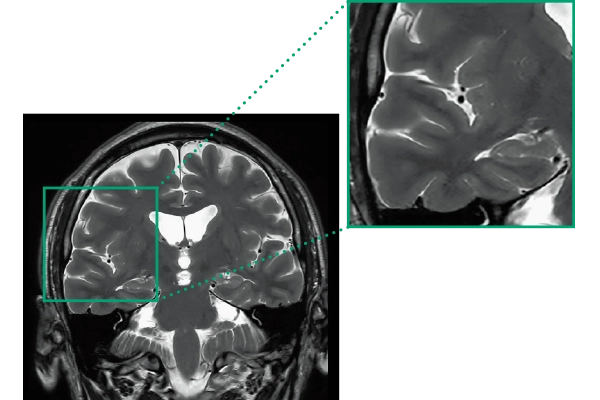

High Resolution

T2WI, 0.56×0.70×3.0mm, 2:28